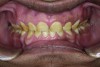

Figure 6. Preoperative maxillary occlusal view.

Figure 6

A thorough clinical examination and analysis were carried out to assess the esthetic and functional problems of the patient (Figure 2 through Figure 7). The medical history was non-contributory, except for mild leukoderma. Temporomandibular joint (TMJ) function was within normal range.

Mounted study casts were used to evaluate occlusion. The relevant findings were as follows2: Facial analysis revealed a canted maxillary occlusal plane and canted dental midline. Dentolabial analysis showed that the maxillary incisors were not adequately visible during repose; it also revealed a reverse smile line, as well as a wide smile showing 12 teeth. Results from the phonetic analysis were that “F” and “V” sounds revealed upper incisal shortening, “M” and “S” pronunciation disclosed a diminished vertical dimension of occlusion (VDO), and “E” sounds showed severe shortening of incisors. Dental analysis revealed thick biotype, asymmetry and inappropriate location of gingival levels and zenith, incorrect axial inclinations, a displeasing width-to-length ratio, and pitted surfaces on most teeth. Interproximal decay was evident on several posterior teeth, as revealed by radiographic analysis. Finally, occlusal examination indicated discrepancy between maximum intercuspation (MIP) and centric relation (CR) as well as a lack of anterior guidance/posterior disclusion.